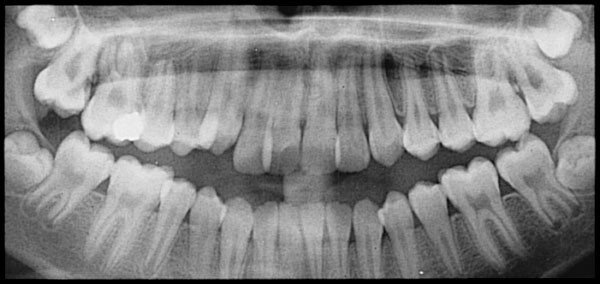

Since no one knows for sure what causes root resorption, it’s hard to know how to prevent it, but since we know there’s a link between orthodontic treatment and root resorption, orthodontists should keep an eye on their patients’ roots. Take regular x-rays and always be on the lookout for decay.